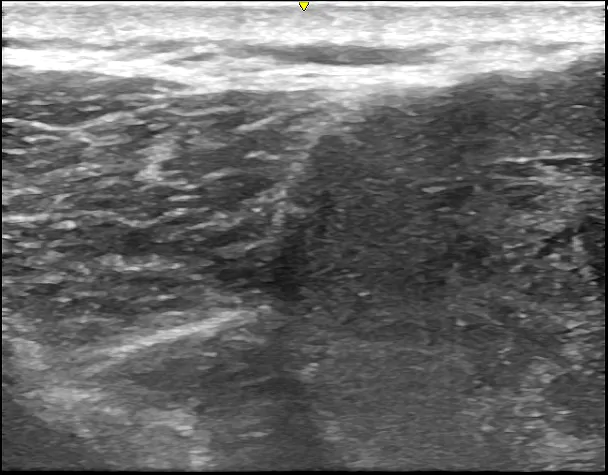

超音波ガイド下で局所麻酔薬を使用し、粉瘤の被膜を剥がした後、小さな切開で角質を排出し、被膜を完全に切除しました。巨大な粉瘤を除去したため、皮下に空間が生じましたが、浸出液がたまらないように2日間ドレーンを挿入しました。

術中 ②被膜を完全に切除